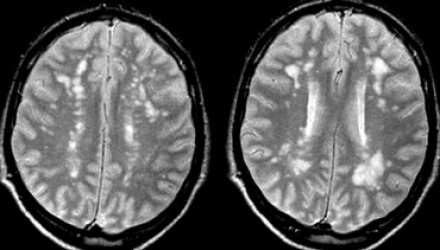

多發(fā)性增強病灶的鑒別診斷

圖片二

在上圖中,是各種多發(fā)性增強白質(zhì)病灶圖像,我們對其中部分病例進行詳細討論。需要說明的是,以下鑒別診斷中提到的疾病與上圖中的圖像并不完全重合。

血管炎

大多數(shù)血管炎性疾病的MRI成像特點是點狀增強。

腦部血管炎常見于系統(tǒng)性紅斑狼瘡、結(jié)節(jié)性多動脈炎(PAN)、白塞病(Behcet)、梅毒、韋格納肉芽腫(Wegener)、干燥綜合征(Sjogren)和原發(fā)性中樞神經(jīng)系統(tǒng)血管炎。

白塞病(Behcet)

白塞病更常見于土耳其患者。典型MRI表現(xiàn)是急性期出現(xiàn)腦干病灶結(jié)節(jié)性增強。

其他疾病的腦轉(zhuǎn)移病灶

其他疾病的腦轉(zhuǎn)移病灶周圍常包裹有水腫帶。

交界區(qū)腦梗死

周圍交界區(qū)腦梗死在病變早期可出現(xiàn)增強病灶。

血管周圍間隙

圖片三:T2加權(quán)成像和FLAIR成像

請查看上圖并描述其病變特點。我們可以看到,在T2加權(quán)成像上,在基底節(jié)上有多個高密度病灶。在FLAIR成像上,這些病灶呈黑暗模糊影,在所有序列成像上,與腦脊液的密度相近(在T1加權(quán)成像上呈低信號)。

結(jié)合信號密度和病灶部位,可以判斷是典型的血管周圍間隙。

圖片四:FLAIR成像

血管周圍間隙是穿透軟腦膜血管周圍的腦脊液間隙。通常位于基底神經(jīng)節(jié)、腦室周圍、前連合附近以及腦干中間。在MR成像圖像上,在所有序列上的密度與腦脊液的密度相近。與其他白質(zhì)損傷病灶不同,血管周圍間隙在FLAIR和PD成像上呈黑暗模糊影,通常比較小,位于前連合附近的除外,此處的血管周圍間隙比較大。

在上圖中,我們可以看到比較寬的血管周圍間隙和在白質(zhì)中有融合的高密度信號病灶。該圖像很好的顯示了血管周圍間隙和白質(zhì)損傷病灶之間的差異。

由于周圍結(jié)構(gòu)組織的萎縮,血管周圍間隙會隨著衰老和高血壓而逐漸增寬。